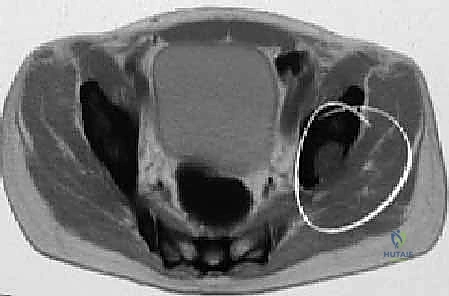

- التصوير المقطعي المحوسب (CT Scan): يوفر صوراً ثلاثية الأبعاد تفصيلية للعظام. يعتبر الأداة الأهم لتقييم مدى تدمير العظم القشري (الطبقة الخارجية الصلبة) وتخطيط حجم ونوع المفصل الاصطناعي بدقة.

- التصوير بالرنين المغناطيسي (MRI): يوضح مدى انتشار الورم داخل نخاع العظم وفي الأنسجة الرخوة المحيطة بالمفصل.